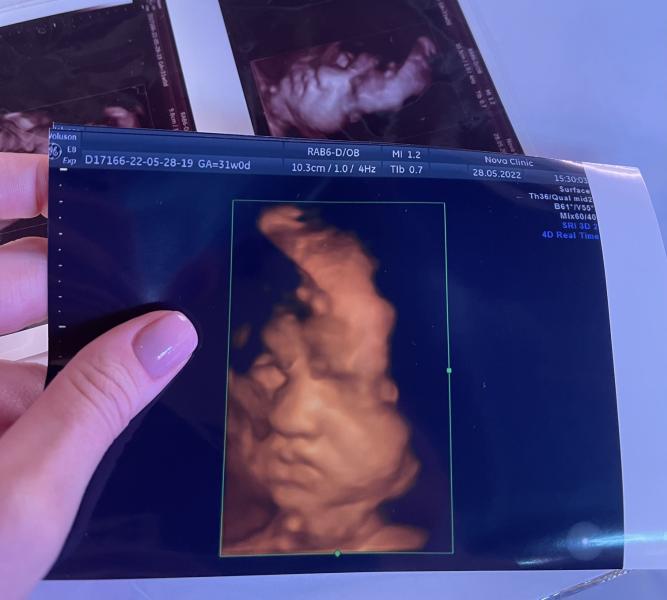

Какое выражение лица у нашего малыша на 3D узи?

Были с мужем на 3D узи 🥰

Наш малыш разрешил на себя посмотреть. Зевал, потягивался, хмурился, показывал язык. Очень ждём наше сокровище 🤍

Сегодня ровно 31 неделя. По узи 31,4.

Весит уже около 1801г (+-263г)

28.05.2022